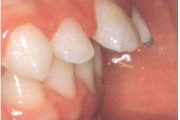

Esimese jäävmolaari ektoopiline lõikumine

) Röntgenülesvõte. Ülemise esimese jäävmolaari lõikumine on takistatud 2. piimamolaari tõttu

Ravijärgne seis. Jäävhammas on täielikult lõikunud.